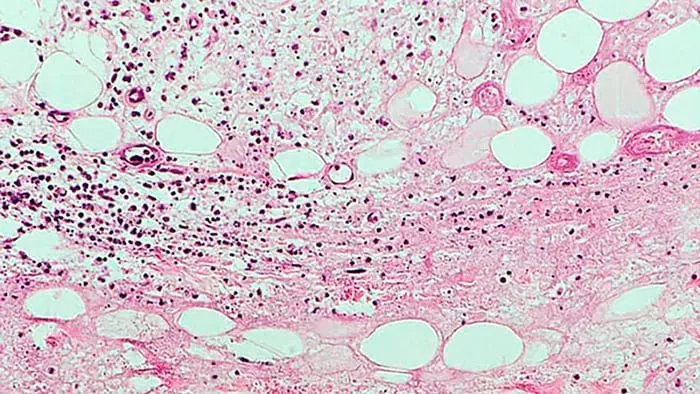

Mô hình minh họa vết loét Buruli với hình dạng ban đầu giống với vết muỗi cắn. Ảnh: Internet

Một số nghiên cứu trước đây đặt giả thiết căn bệnh có thể lây qua đường nước, muỗi hoặc thú có túi. Ngoài ra, động vật bản địa và gia súc bao gồm chó, mèo, possum và Kaola đa phần đều làm phát triển bệnh, nhưng không biết liệu chúng có làm lây lan bệnh hay không?